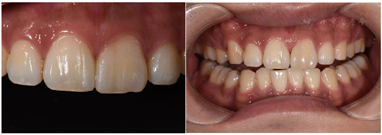

11、21贴面试戴,邻接可,外形佳,边缘密合,色泽与天然牙匹配,患者满意同意粘接,粘结后检查正中颌、前伸颌及侧方颌,咬合无明显异常。粘结后3个月复诊检查,11、21牙邻面贴面固定在位无折裂,边缘密合且无明显着色、修复体颜色无明显改变,检查正中颌、前伸颌及侧方颌,咬合无明显异常。

治疗计划为11、21贴面修复(邻面贴面)或正畸治疗。患者选择行贴面修复;龈上洁治,排龈,备牙前进行常规术前照相及比色(VITA2M2)。牙体预备:由11、21近中面扩展至唇近中线角,预备量约0.3 mm,基牙颈部预备与牙龈外形保持一致,肩台呈浅凹形,比色(VITA2M2)口扫;贴面试戴,邻接可,外形佳,与牙面边缘密合,色泽与天然牙匹配,患者满意同意粘接,粘结后检查正中颌、前伸颌及侧方颌,咬合无明显异常。见图3,图4,图5,图6,图7。